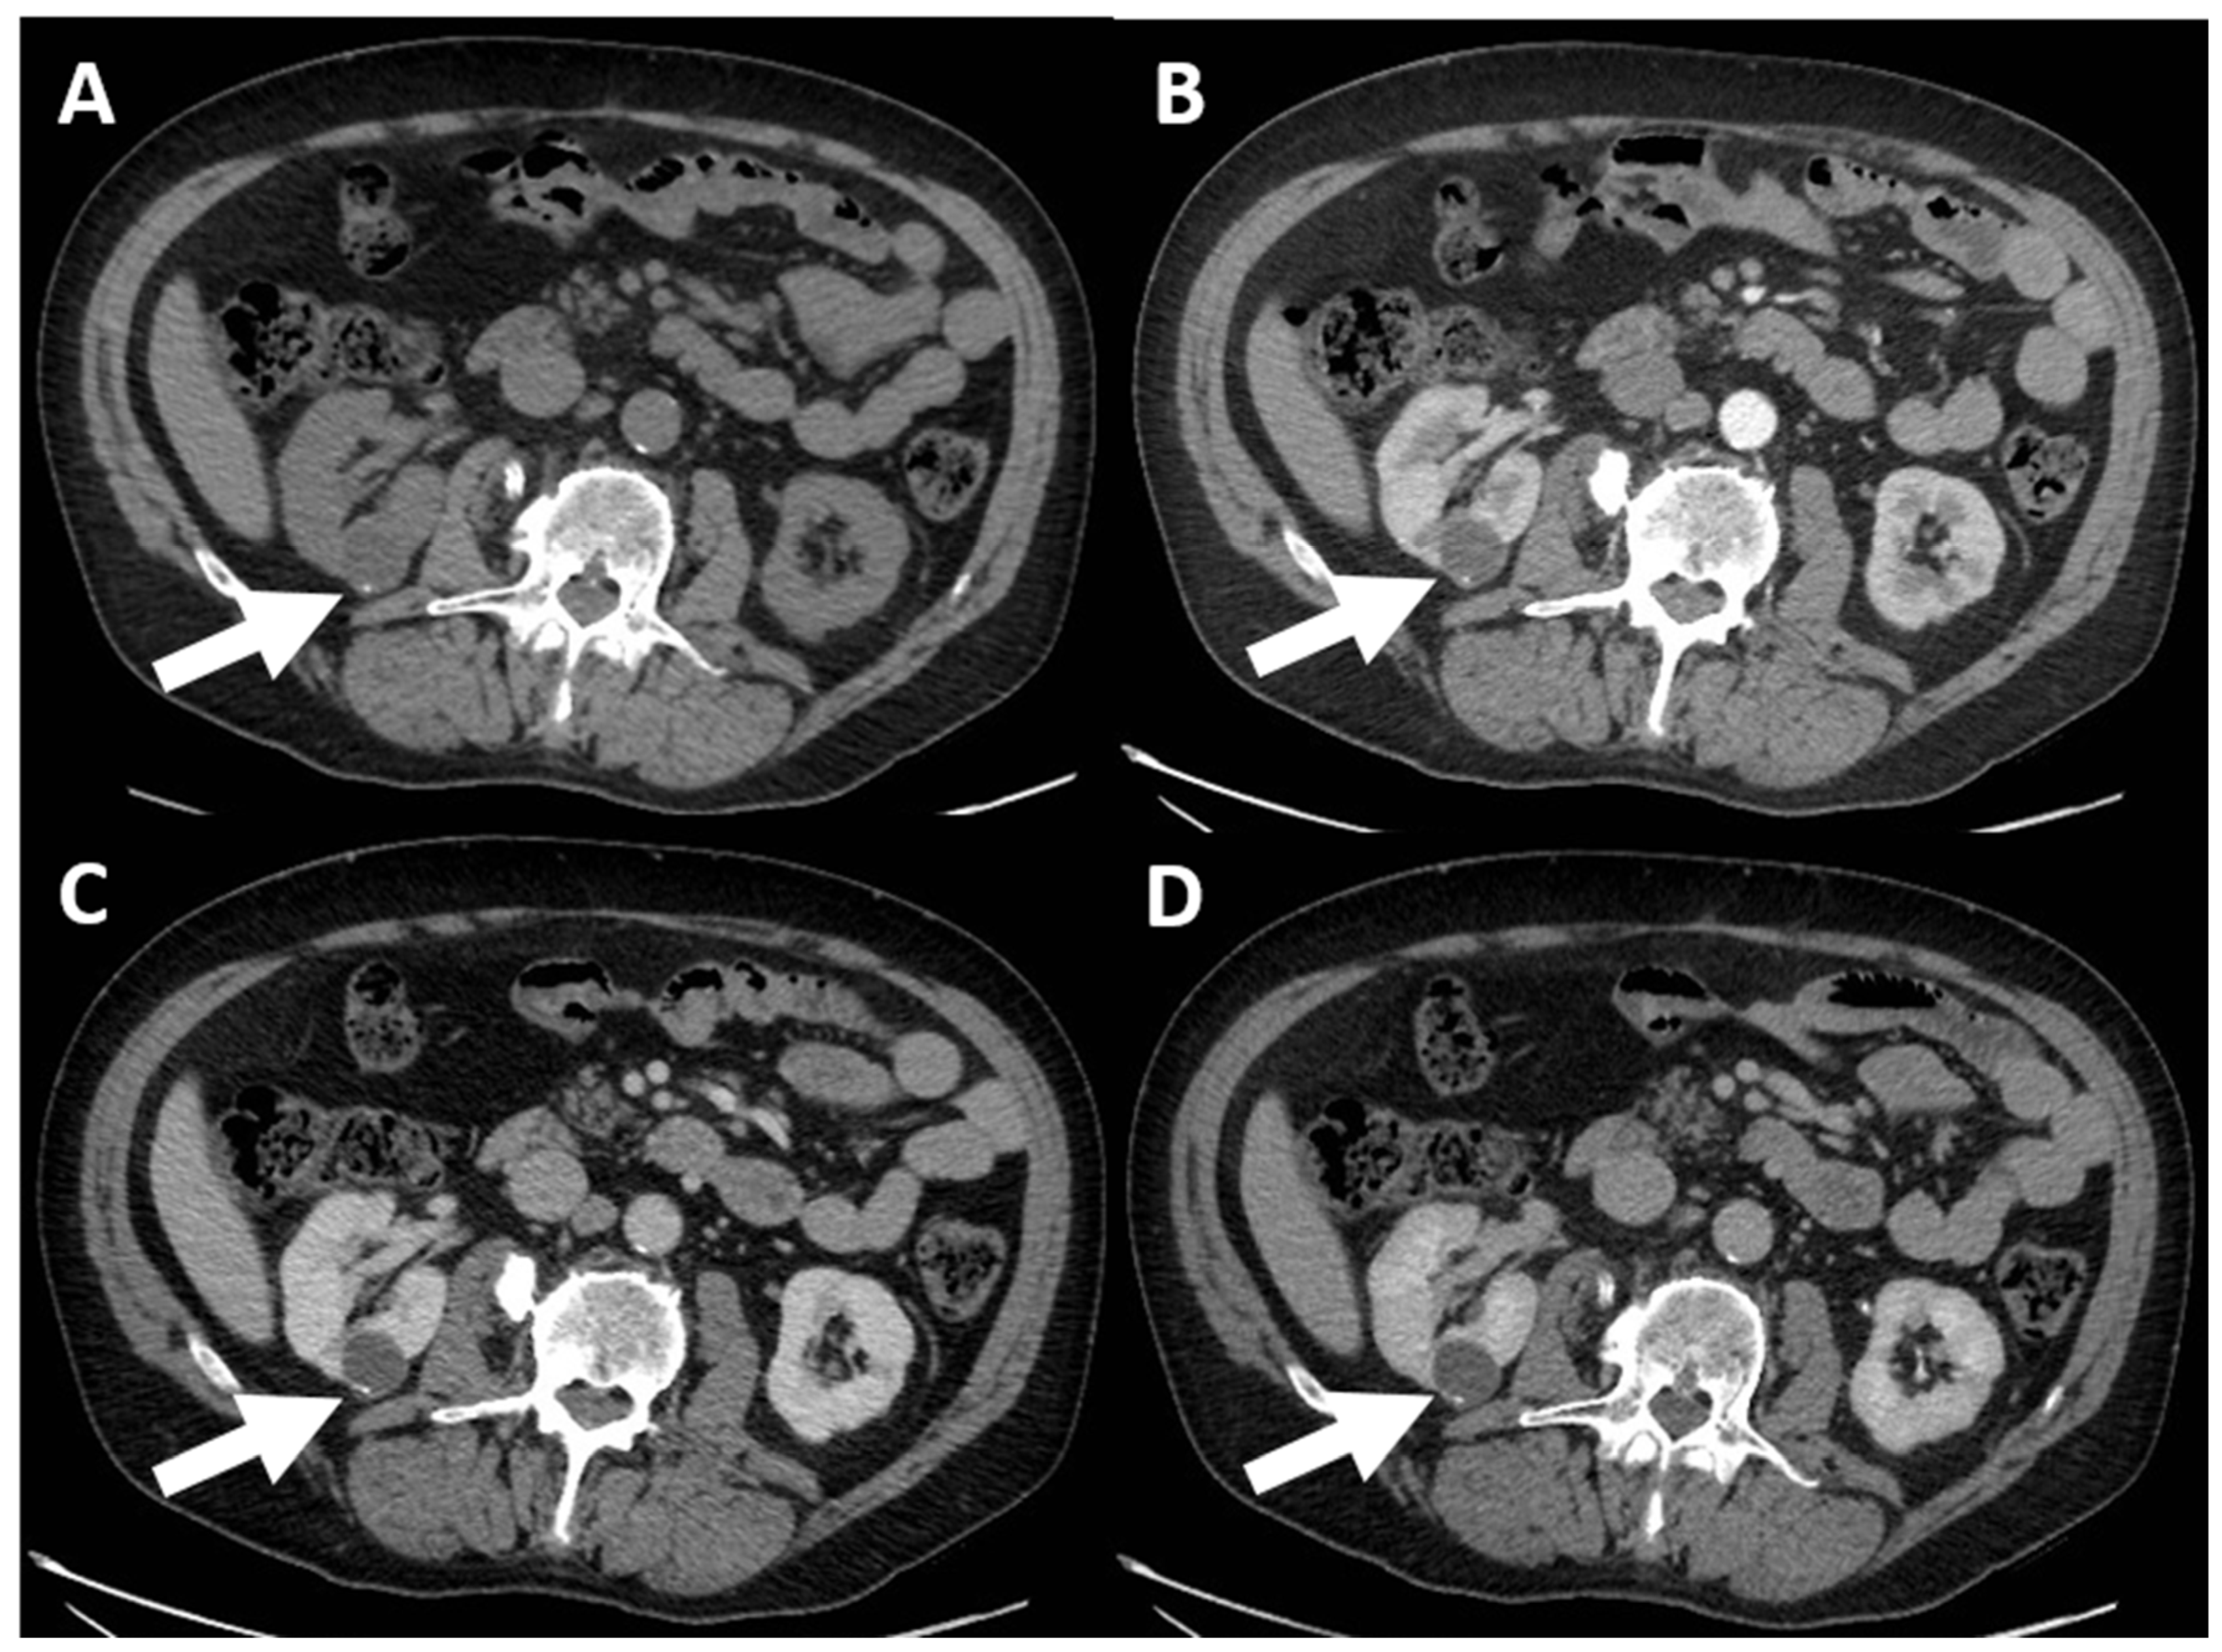

- (d) Class III: indeterminate cystic mass, which includes cystic masses characterized by one or more thickened (≥4 mm) or enhancing and irregular (≤3 mm and with convex marginal protrusions) walls or septa [91]. Bosniak III masses (Figure 4) are “potentially” malignant in that they have an intermediate probability of malignancy (about 55%) [97]. Therefore, urologic consultation should be considered for possible partial nephrectomy or radiofrequency ablation in candidates unfit for surgery [99].